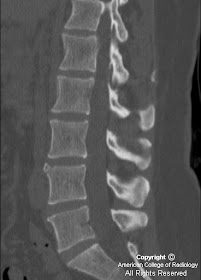

12+ Limbus Fracture Radiology Gif. Limbus is a latin word meaning border. During the first two decades, the appearance and physiology of the cervical spine varies tremendously.

It is usually caused by a fall onto an outstretched hand (foosh). Limbus vertebral fracture is an uncommon injury described in adolescents. Presentation material for educational purposes only. The distal radial fracture is the most common fracture of the forearm and accounts for approximately 16% of all skeletal fractures.